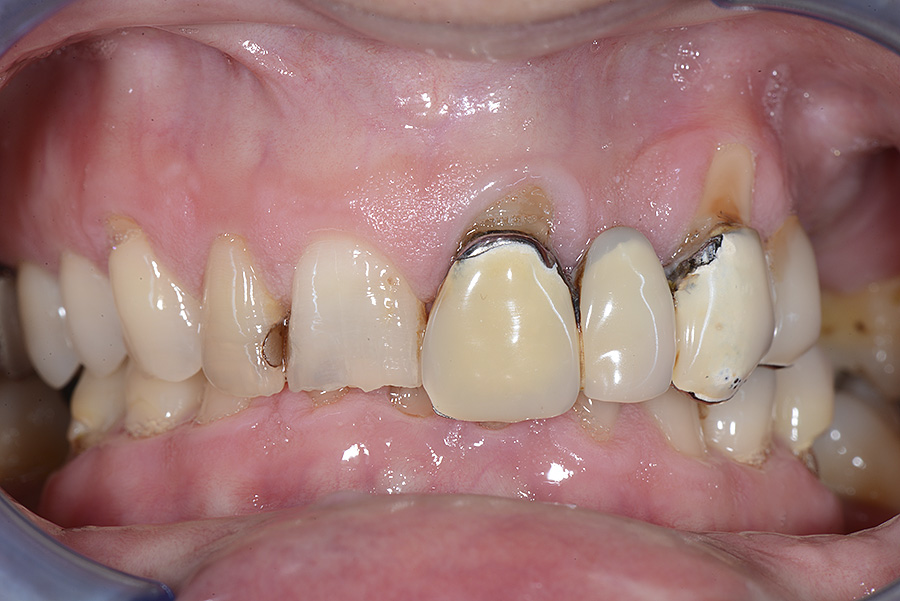

PREMESSA: in seguito all’estrazione dell’incisivo laterale superiore di destra, resasi necessaria per cause batteriche, si decide di affrontare il caso con il posizionamento di un impianto in sostituzione dell’elemento mancante dopo guarigione del sito infetto. Con tecniche rigenerative sia dei tessuti ossei mancanti a causa dell’infezione pregressa, sia dei tessuti gengivali che appaiono inizialmente troppo spostati in alto, si ripristina una corretta morfologia delle parabole (contorni) gengivali e delle papille interdentali (triangoli di gengiva tra due denti vicini).

Vengono utilizzati 2 tipi di provvisori: il primo, cementato ai denti vicini, viene utilizzato dal momento dell’estrazione del dente fino ad impianto osteointegrato (circa 6 mesi); il secondo, avvitato direttamente all’impianto, ha una funzione di prova estetica ma soprattutto di guida per la maturazione dei tessuti gengivali peri-implantari portandoli verso la maturazione completa prima di posizionare la corona finale in disilicato di litio.